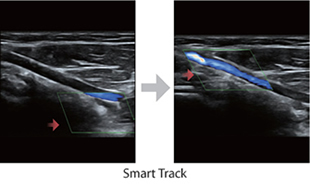

Smart Track

Funkcja Smart Track zapewnia szybk? i inteligentn? optymalizacj? obrazów naczyń krwiono?nych zaledwie po jednym klikni?ciu. Umo?liwia optymalizacj? w trybach Dopplera Kolorowego, Power Dopplera i Dopplera spektralnego PW poprzez samodzieln? detekcj? naczynia i skrócenie czasu niektórych etapów badania. W ten sposób cykl czynno?ci podczas badania naczyń krwiono?nych zosta? uproszczony z jednoczesnym zachowaniem optymalnego obrazowania.